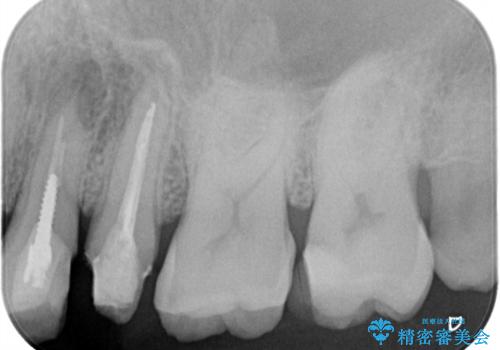

レントゲン上からも、歯の中(根管)が汚れている可能性があることをご説明したところ、根管治療からやり直しをすることになりました。

根管治療について

保険根管治療は回数がかかることが多く、終了予定がわかりにくいです。

当院では、根管治療は長い時間のご予約を頂き、多くの場合2~3回で終わります。

根管治療は歯内の治療なので患者様には見えない場所ですが、ここが細菌で汚染されると激しい痛みや長引く違和感の原因になります。

当院では、清潔な治療を徹底し、顕微鏡を使用した精密な治療を行っています。

症状や根管の状態により、治療金額が異なります(5~10万円目安)。治療回数による費用負担の増減はありません。